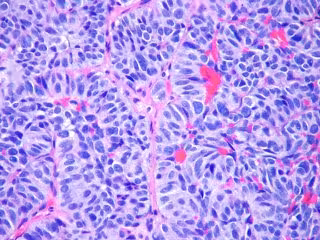

Metástasis pulmón

FLICKR/PULMONARY PATHOLOGY/ CC BY-SA 2.0